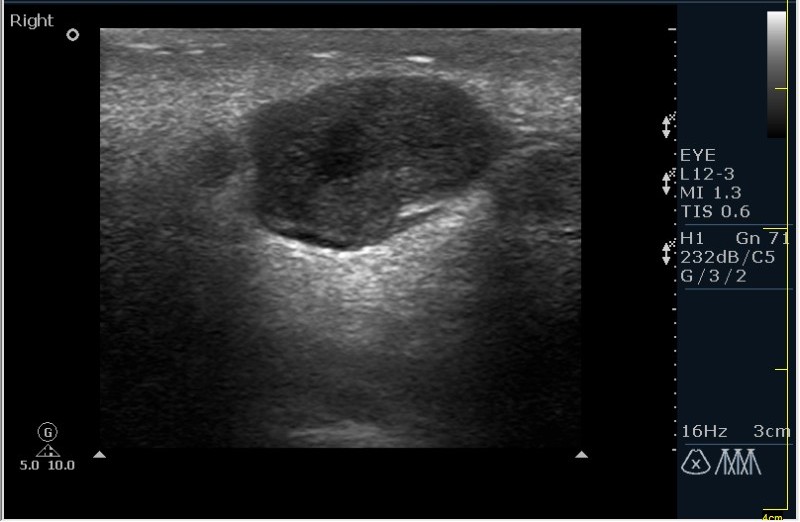

Мужчина 68 лет, направлен на УЗИ правой слюнной железы. Жалобы на пальпируемое, малоболезненное плотное образование за правым ухом.

Солидное!!!! Я тоже ТАБ хотел сделать, но ЛОР заказал КТ... А какие мысли будут?

Первая мысль о очаговом воспалении, деструктивной фазе, но нет клиники.

Тумор?

Клиники нет, тумор на первом месте. В принципе КТ (или МРТ) заказывают для диффиренцировки зло/добро. Плюс посмотреть есть ли локальное растпространение. Но в данном случае я думаю УЗИ с ТАБ было бы достаточно.